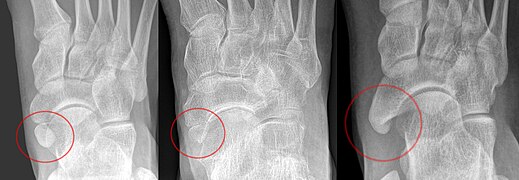

Un os naviculaire accessoire se développe parfois devant la cheville vers l'intérieur du pied. Cet os peut être présent chez environ 2 à 21 % de la population générale et est généralement asymptomatique[10],[11],[12]. Lorsqu’il est symptomatique, une intervention chirurgicale peut être nécessaire.

La classification Geist divise les os naviculaires accessoires en trois types[12] :

- Type 1 : os sésamoïde de 2 à 3 mmm dans le tendon distal du muscle tibial postérieur, généralement asymptomatique,

- Type 2 : osselet triangulaire ou en forme de cœur mesurant jusqu'à 12 mm, qui représente un centre d'ossification secondaire relié à la tubérosité naviculaire par un connecteur 1–2 mm de fibrocartilage ou de cartilage hyalin, des parties du tendon du muscle tibial postérieur s'insèrent parfois sur l'osselet accessoire, ce qui peut provoquer un dysfonctionnement et donc des symptômes,

- Type 3 : Un os corné présentant une tubérosité naviculaire médiale élargie, parfois symptomatique en raison de la formation d’oignons.

Os trigone

L'os trigone (ou astragale surnuméraire ou astragale accessoire) provient de l'échec de la fusion du tubercule latéral du processus postérieur du talus . On estime qu'il est présent chez 7 à 25 % des adultes[9].

Il peut être confondu avec une fracture par avulsion des tubercules latéral ou médial du processus postérieur du talus.

Dans la plupart des cas, l'os trigone passe inaperçu, mais dans certaines blessures à la cheville, il peut rester coincé entre le talon et les os de la cheville provocant une inflammation des structures environnantes[13].